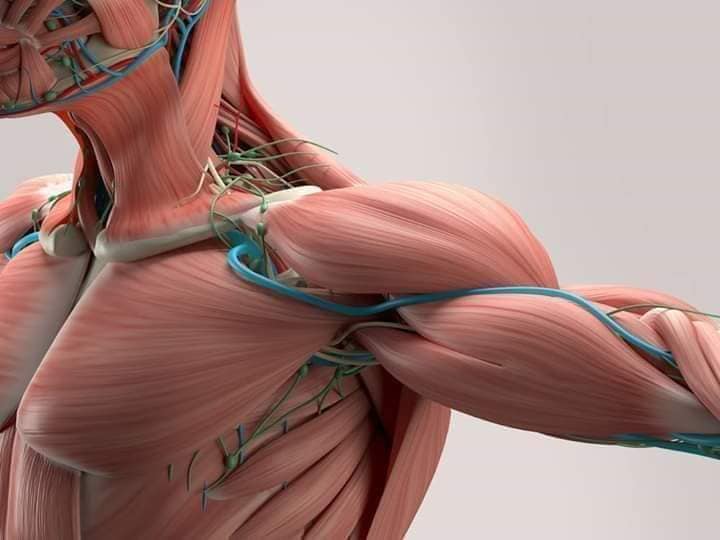

М'язова система (мускулатура) — система органів вищих тварин і людини, утворена скелетними м'язами, які, скорочуючись, приводять в рух кістки скелета, завдяки якій організмом здійснюється рух в усіх його проявах. М'язова система відсутня в одноклітинних і губок, але і ці тварини не позбавлені спроможності рухатись.

М'язова система являє собою сукупність здатних до скорочення м'язових волокон, об'єднаних в жмуток, який формує особливі органи — м'язи або ж самостійно входять до складу внутрішніх органів. Маса м'язів набагато більша, ніж маса інших органів: у хребетних тварин вона може досягати 50 % маси всього тіла, у дорослої людини — до 40 %. М'язова тканина тварин також називається м'ясо і поряд з деякими іншими складовими тіл тварин вживається в їжу. В м'язових тканинах відбувається перетворення хімічної енергії в механічну енергію і теплоту.

Скелетно-м'язова система людини (синоніми: Опорно-рухова система, опорно-руховий апарат, кістково-м'язова система, локомоторна система) — комплекс структур який утворює каркас, надає форму організму, дає йому опору та забезпечує захист внутрішніх органів і можливість пересування у просторі. Це функціональна сукупність кісток скелета, їх з'єднань (суглобів і сінартрозів), і соматичної мускулатури з допоміжними пристосуваннями, які здійснюють за допомогою нервової регуляції локомоції, підтримання пози, міміки та інших рухових діях, поряд з іншими системами органів утворює людське тіло.

М'язова система людини є однією з основних систем організму, що відповідає за рухи, підтримання пози та стабільність. Вона складається з понад 600 м'язів, які можна класифікувати на скелетні, гладкі та серцеві м'язи. Скелетні м'язи, які є об'єктом нашого детального розгляду, дозволяють контролювати навколишній світ і виконувати різноманітні рухи. Особливу увагу в нашій статті буде приділено шейним і спинним м'язам, оскільки ці групи м'язів мають критичне значення для підтримання правильного постава та функціонування хребта.